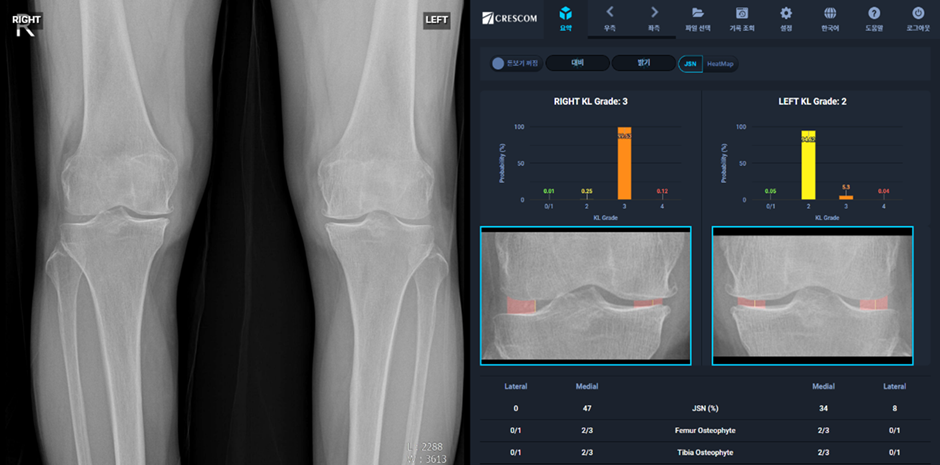

24-04-17 크레스콤, 국내 최초 무릎 관절염 심각도 정량화 자동분석 인공지능 소프트웨어 ‘MediAI-…

근골격계 의료데이터 인공지능 분석 솔루션에 특화된 주식회사 크레스콤(대표 이재준)은 지난 5일 KL 등급 기반의 무릎 관절..

23-11-24 크레스콤의 인공지능 소프트웨어 MediAI-OA, 무릎 골관절염 심각도 정량적 평가 솔루션에…

(사진: 인공지능 무릎 골관절염 심각도 정량적 평가 솔루션 MediAI-OA 논문 게재_ⓒ Crescom Co., Ltd...